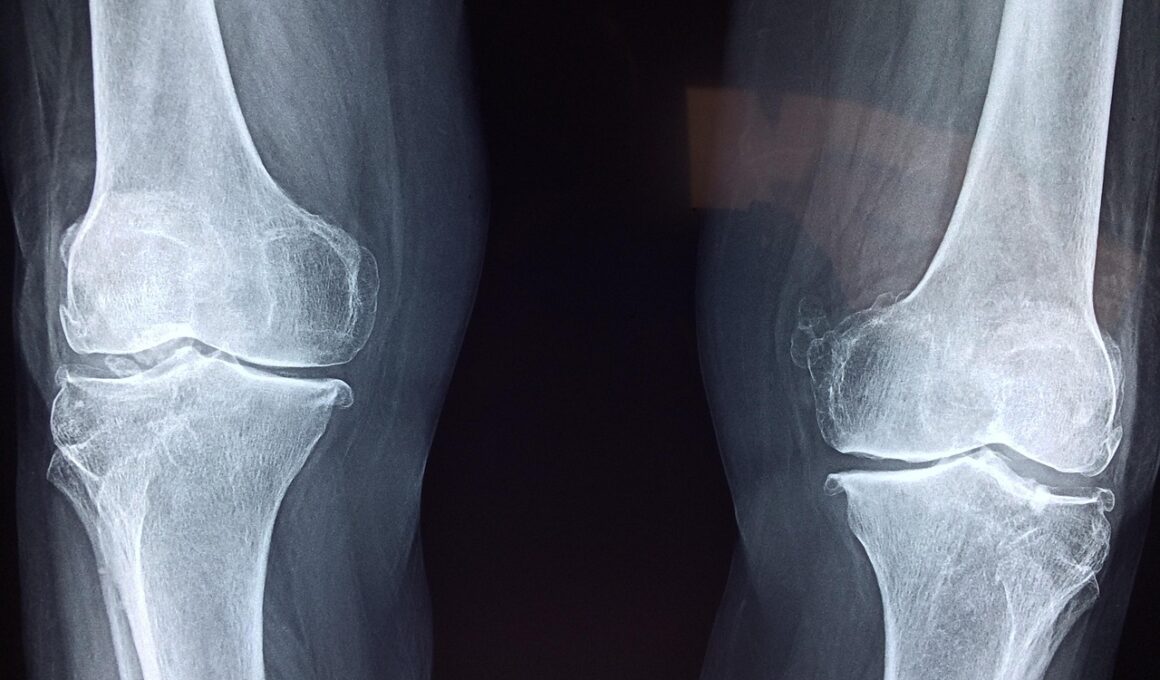

Higher bone density correlates with a reduced risk of osteoporosis and fractures. Research shows that HIIT promotes bone strength by stimulating bone formation through increased mechanical loading. The activity-level of HIIT effectively engages multiple muscle groups such as lower body, upper body, and core. This comprehensive engagement can lead to increased bone mineral density (BMD) across various sites including the hip, spine, and limbs. Enhanced BMD results from the dynamic exercises incorporated into HIIT routines, which force bones to continually adjust and adapt. Various studies highlight that older adults who participate in high-intensity resistance training, often seen in HIIT, significantly improve their bone health and reduce fracture risks. Exercises like jumping or sprinting stimulate responses from the osteocytes, which can enhance bone remodeling and health over time. Furthermore, individuals beginning HIIT at a younger age can expect lasting benefits, as higher bone density established during youth often translates into better bone health in later years. In conclusion, incorporating HIIT into one’s fitness regimen can prove essential in mitigating age-related bone loss and cardiovascular disease risks.